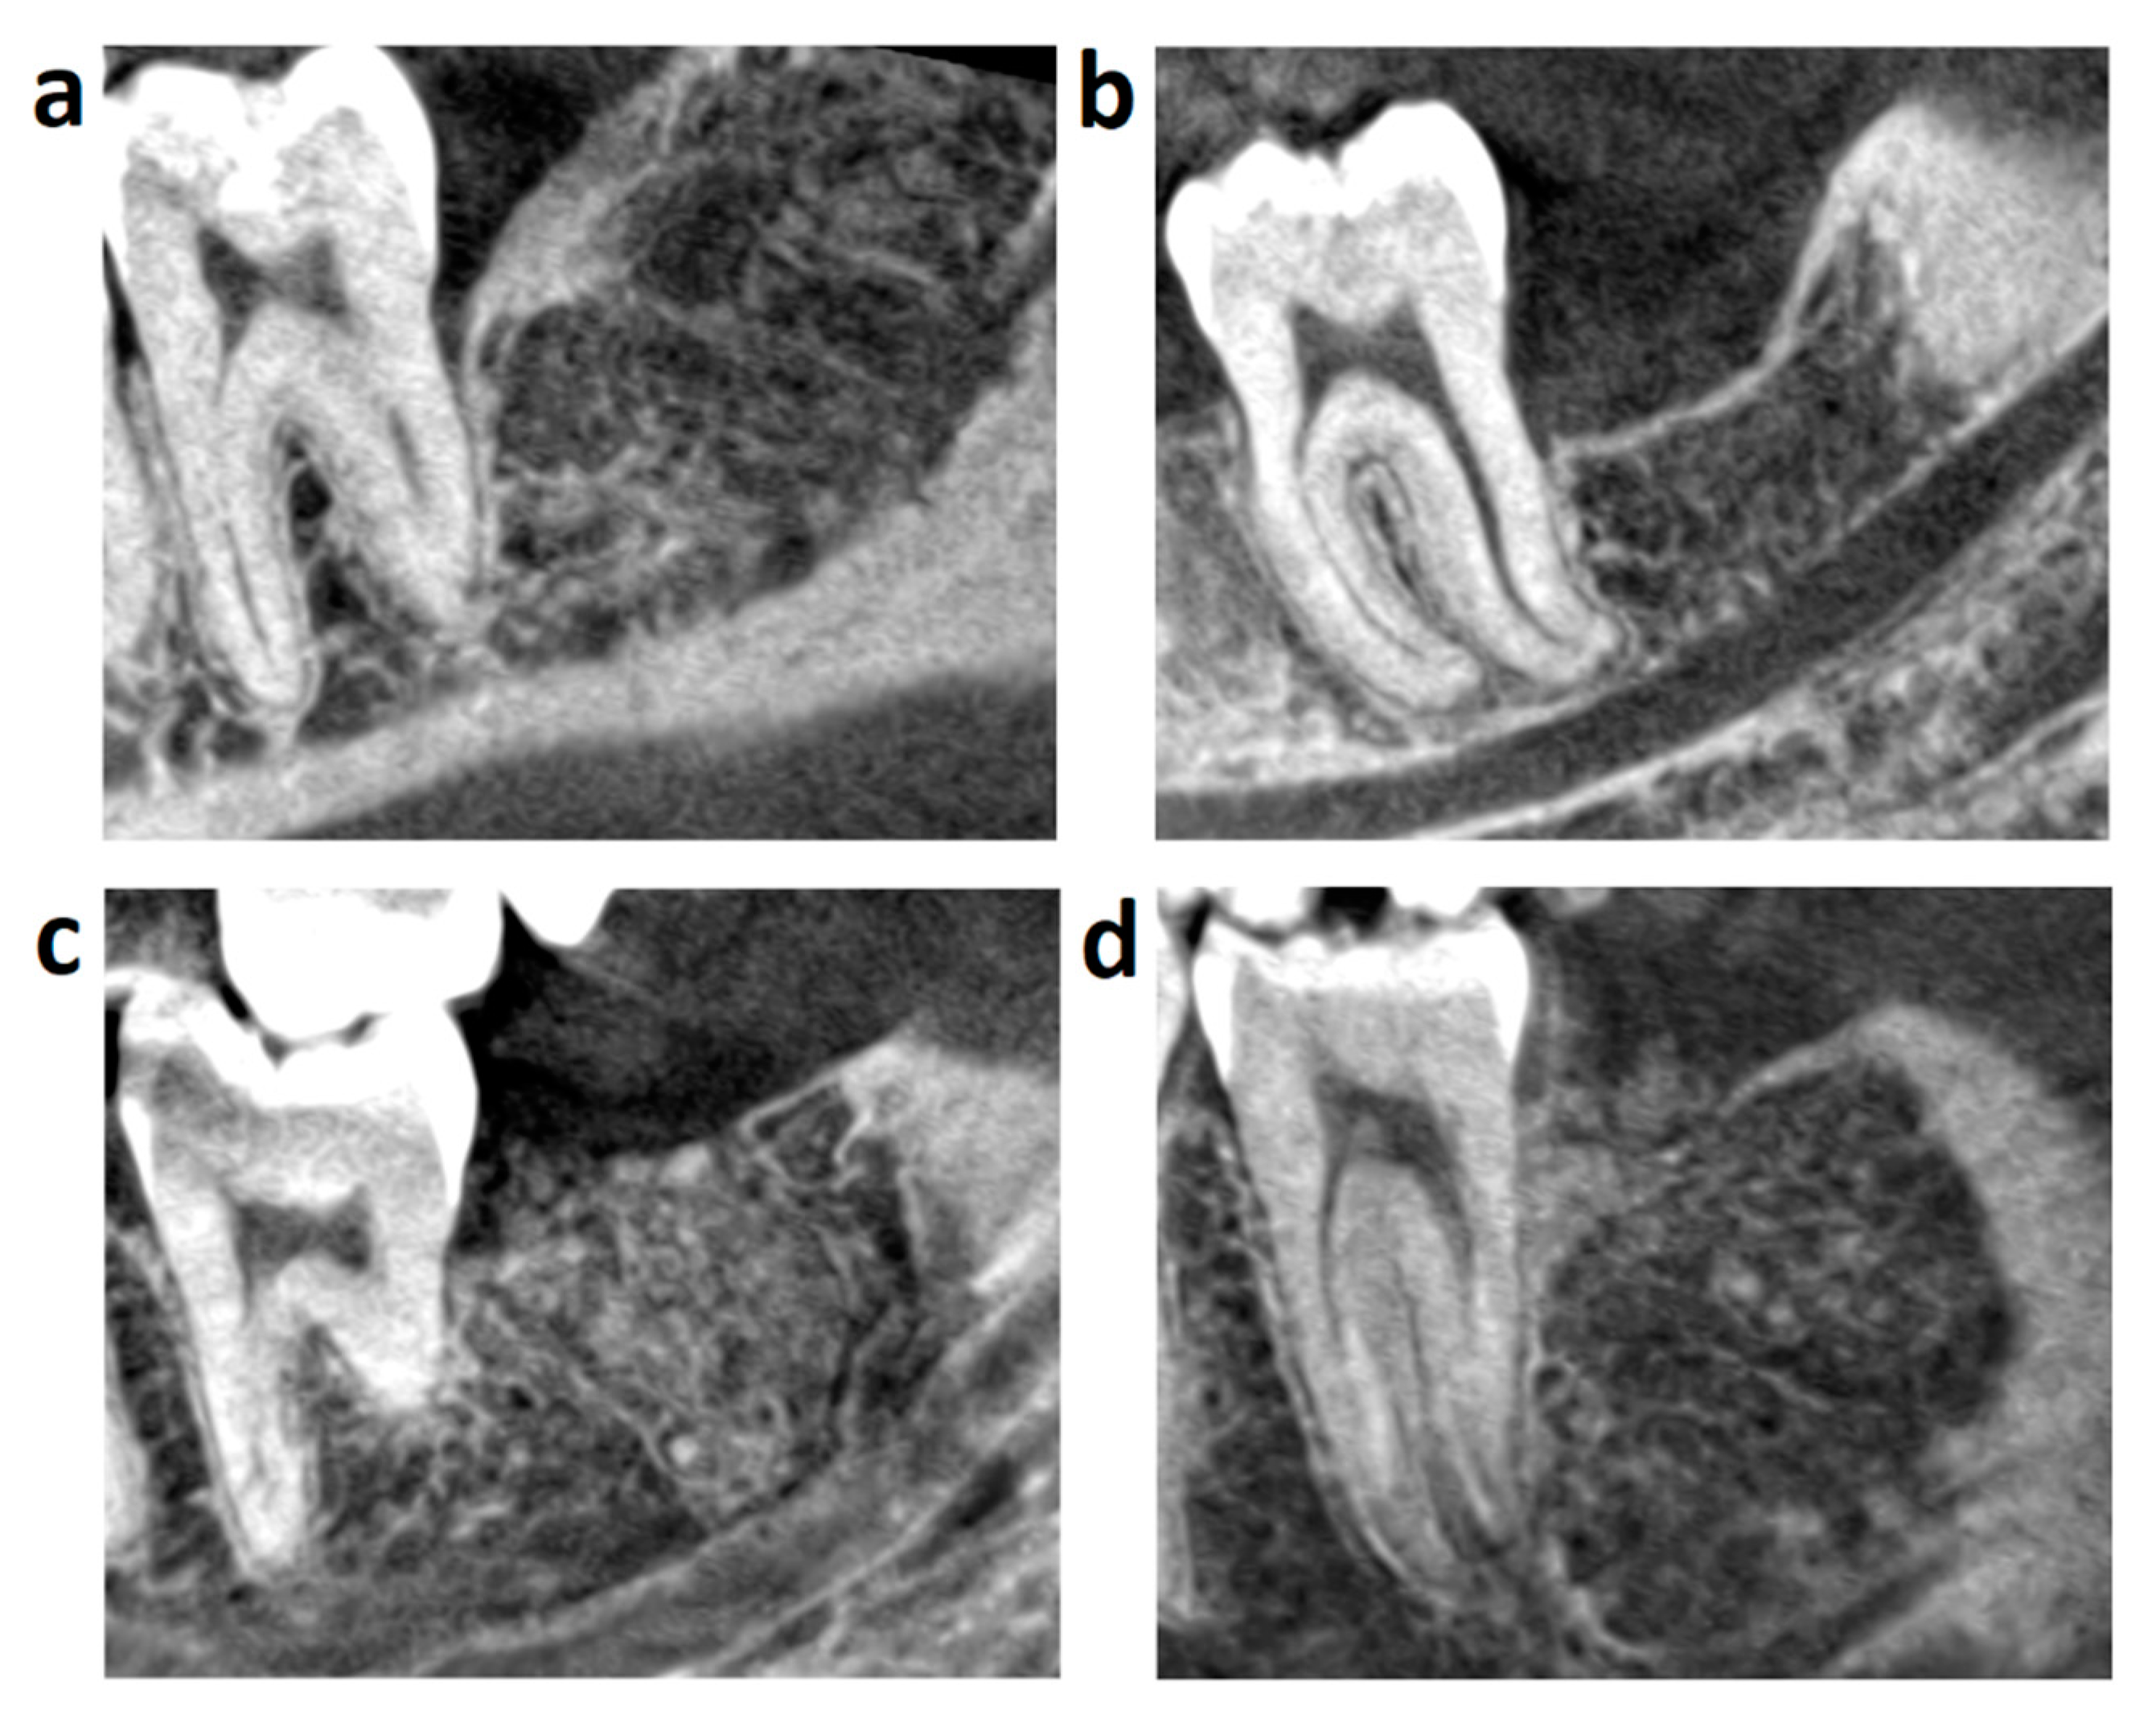

- Simonffy, L.; Minya, F.; Trimmel, B.; Lacza, Z.; Dobo-Nagy, C. Albumin-Impregnated Allograft Filling of Surgical Extraction Sockets Achieves Better Bone Remodeling Than Filling with Either Blood Clot or Bovine Xenograft. Int. J. Oral Maxillofac. Implant. 2020, 35, 297–304. [Google Scholar] [CrossRef] [PubMed]

- Kivovics, M.; Szabó, B.T.; Németh, O.; Iványi, D.; Trimmel, B.; Szmirnova, I.; Orhan, K.; Mijiritsky, E.; Szabó, G.; Dobó-Nagy, C. Comparison between Micro-Computed Tomography and Cone-Beam Computed Tomography in the Assessment of Bone Quality and a Long-Term Volumetric Study of the Augmented Sinus Grafted with an Albumin Impregnated Allograft. J. Clin. Med. 2020, 9, 303. [Google Scholar] [CrossRef] [PubMed]